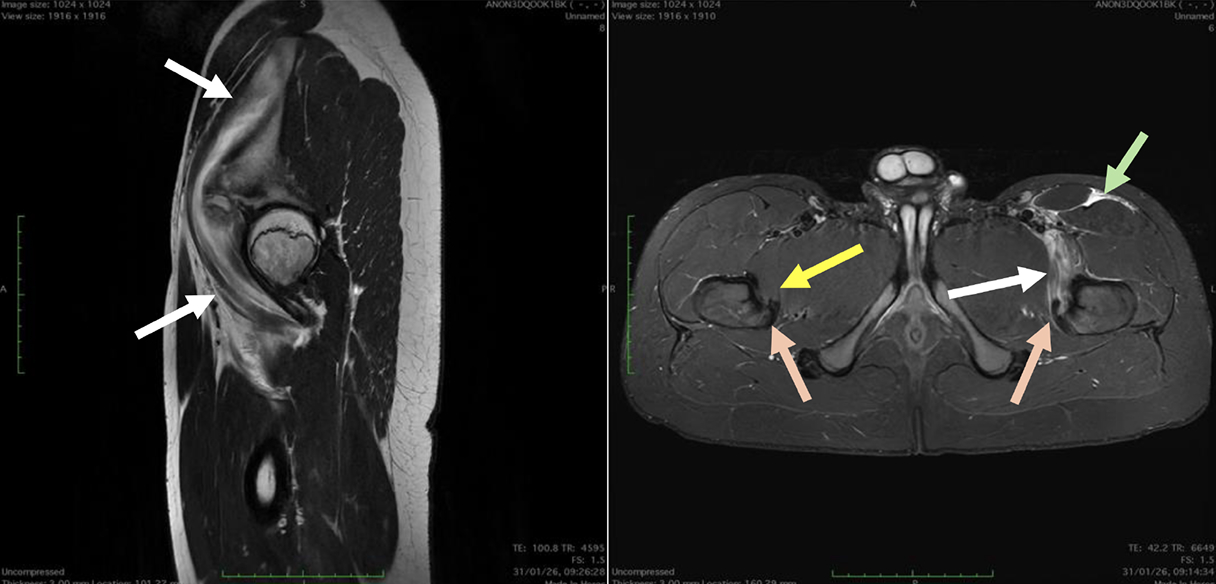

Fifty shades of grey

Caso condiviso da Marcello De Santis